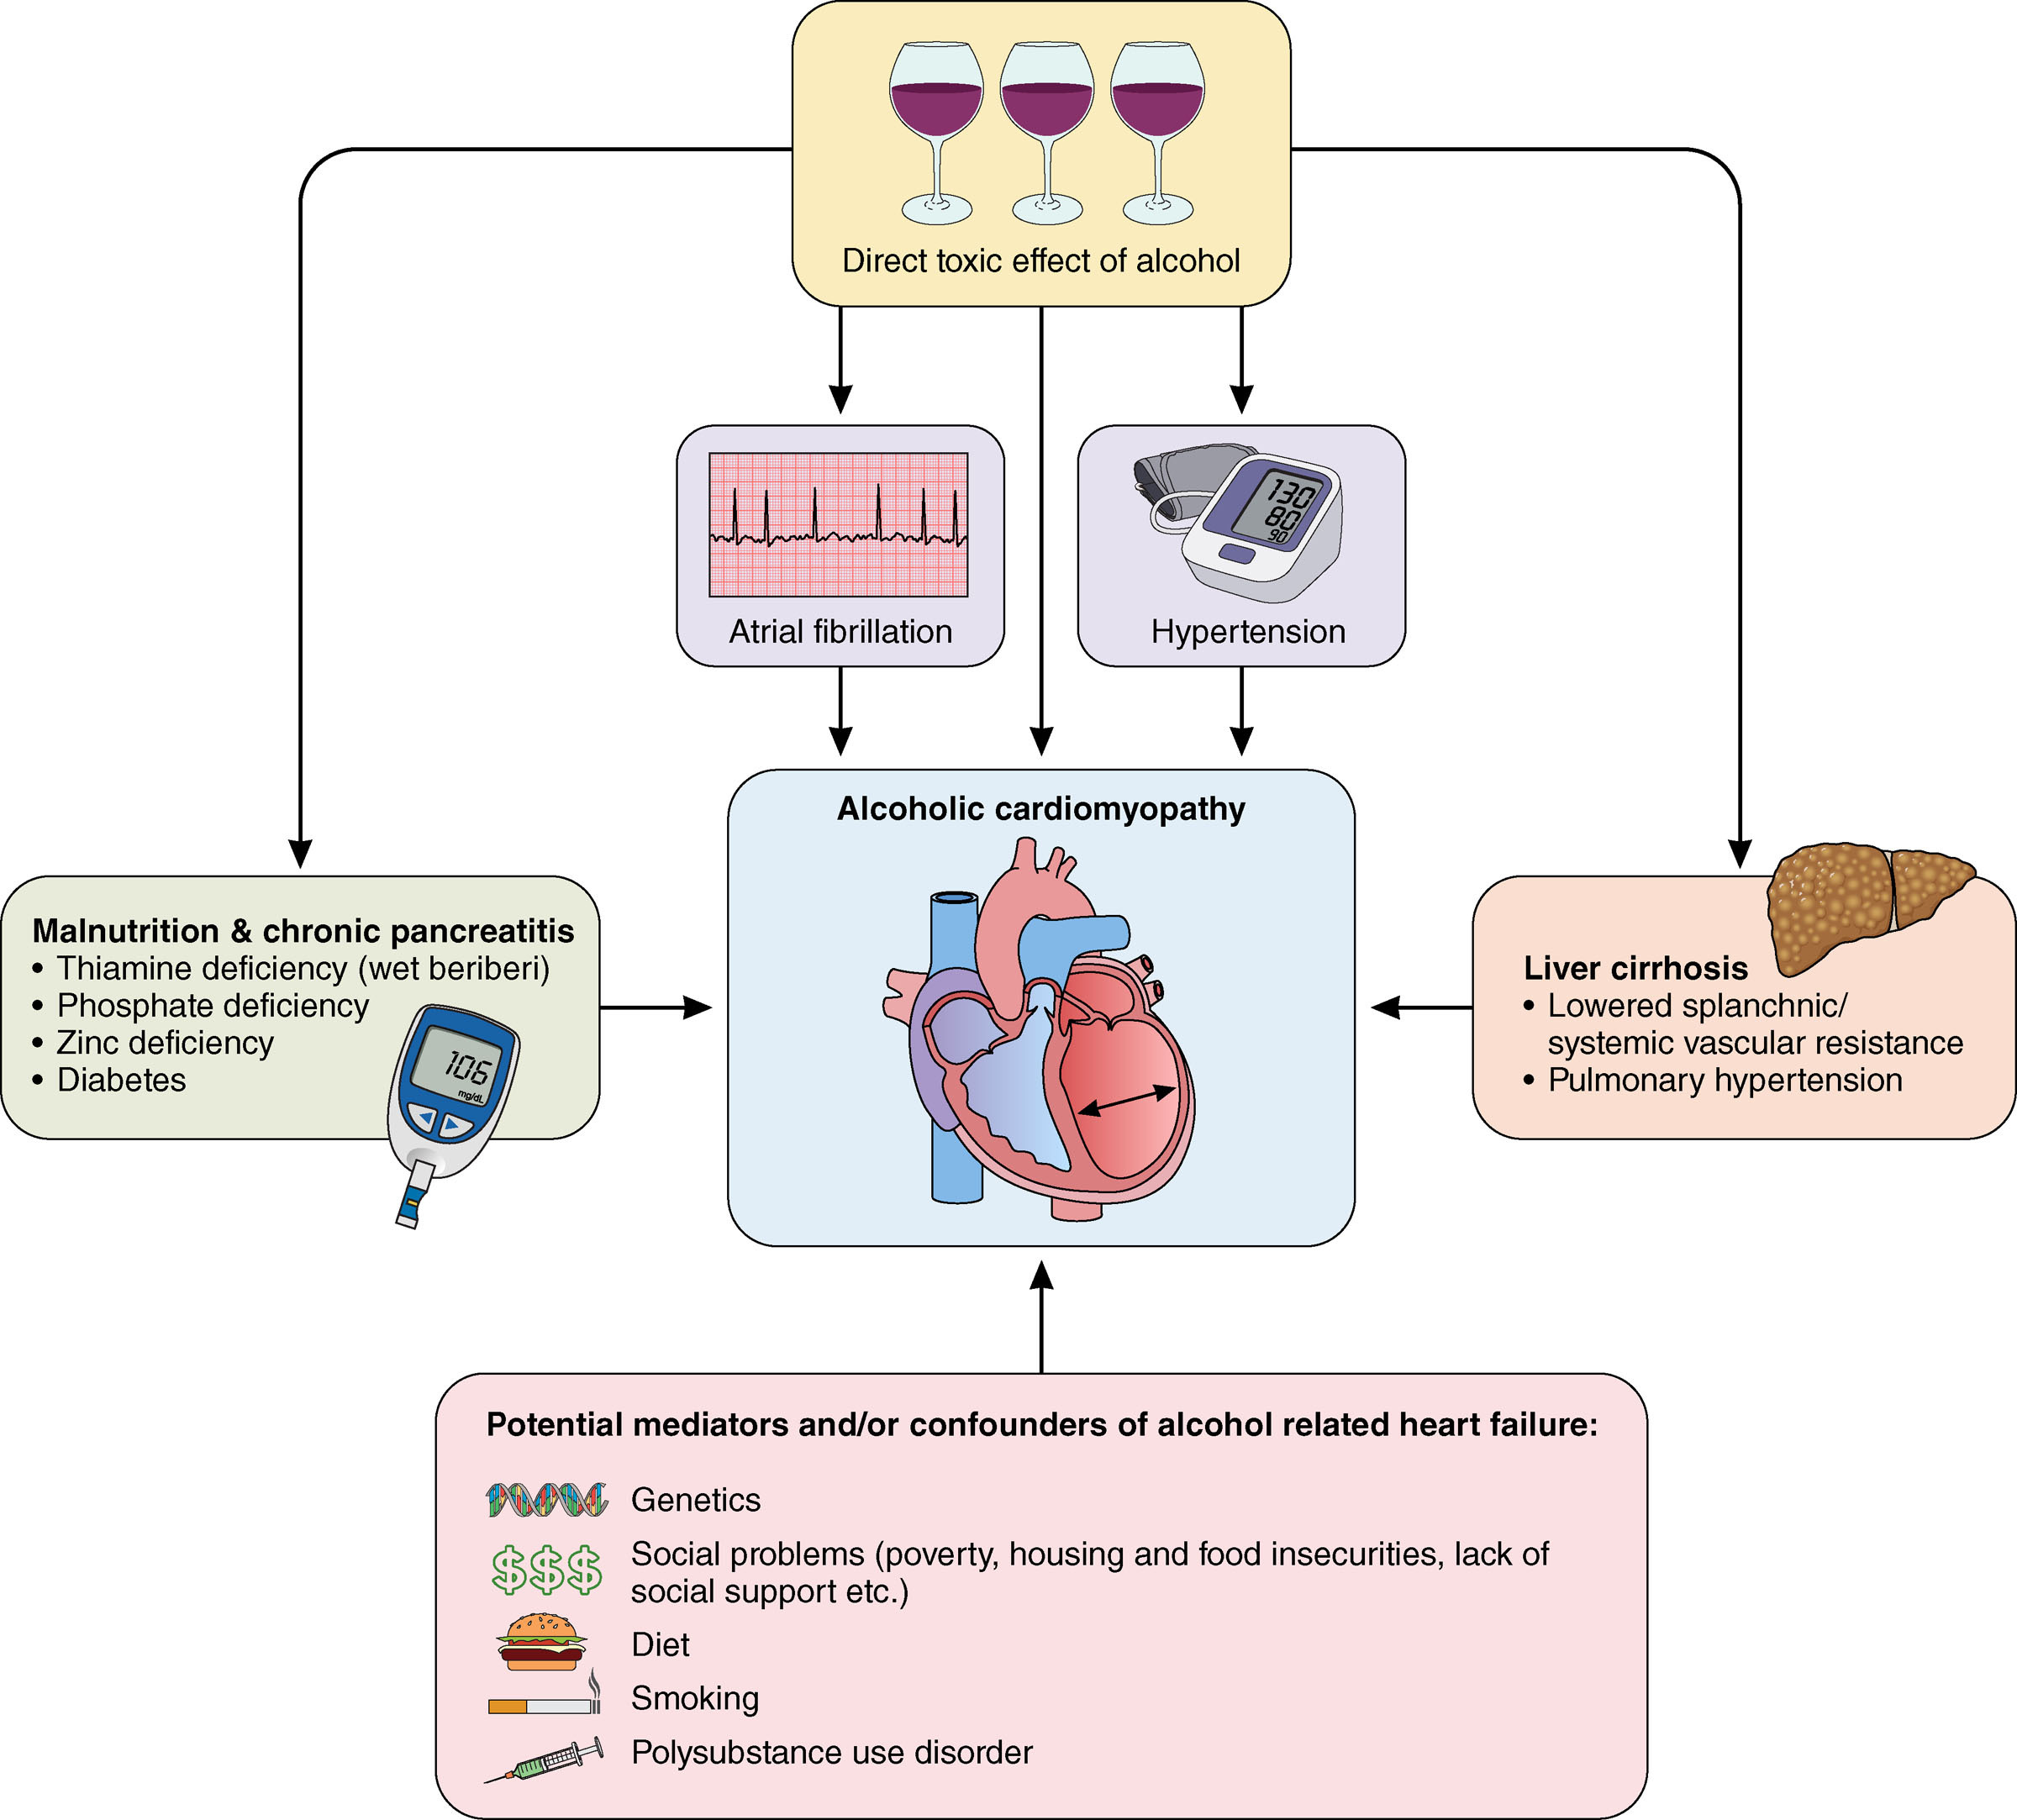

alcoholic cardiomyopathy is a (type) and (ir/reversible)

dilated & reversible w/ cessation of drinking

alcohol use causes a ir/reversible ____ cardiomyopathy

reversible dilated cardiomyopathy